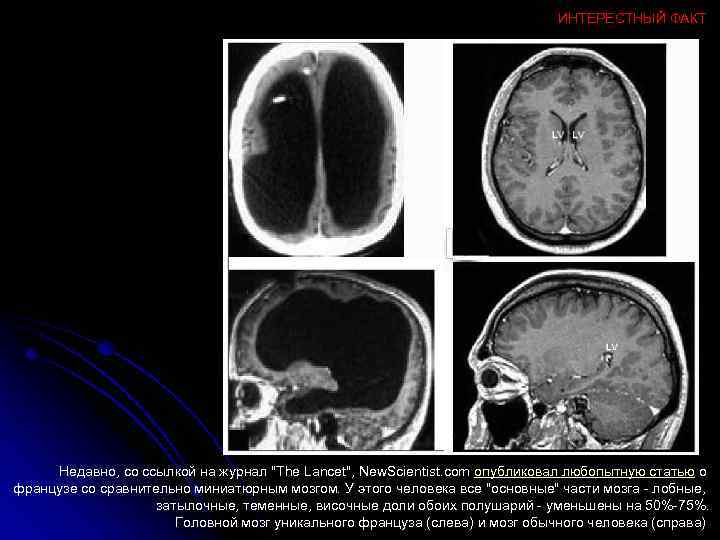

ИНТЕРЕСТНЫЙ ФАКТ Недавно, со ссылкой на журнал "The Lancet", New. Scientist. com опубликовал любопытную статью о французе со сравнительно миниатюрным мозгом. У этого человека все "основные" части мозга - лобные, затылочные, теменные, височные доли обоих полушарий - уменьшены на 50%-75%. Головной мозг уникального француза (слева) и мозг обычного человека (справа)